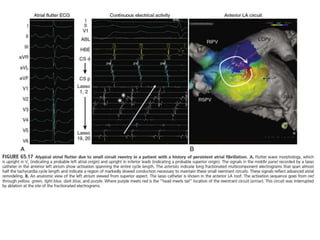

Atrial Flutter or Macroreentrant Atrial

Tachycardia

CAVO-TRICUSPID ISTHMUS DEPENDENT FLUTTER.

Typical flutter is as a macroreentrant circuit within the

right atrium. It can be considered to be a broad activation

wavefront rotating between the tricuspid annulus (TA)

anteriorly and the crista terminalis-eustachian

ridge/inferior vena cava (IVC) posteriorly .

In the most common form (approximately 90%) the circuit

rotates in a counterclockwise direction when viewed in the

frontal plane.

In 10%, rotation is clockwise.

 The ECG of typical counterclockwise AFL is

characterized by the classic inferior lead flutter wave

appearance (“saw-tooth” pattern) demonstrating an initial

gradual downsloping segment followed by a deeply

inverted component with a terminal positive component.

 In the precordial leads, V1 classically demonstrates an

initial isoelectric component followed by an upright

component.

 With progression across the precordial leads, the initial

component becomes inverted and the second

component isoelectric such that V5 and V6 demonstrate

an inverted flutter wave.

 Lead I is low amplitude/isoelectric and aVL usually

upright.